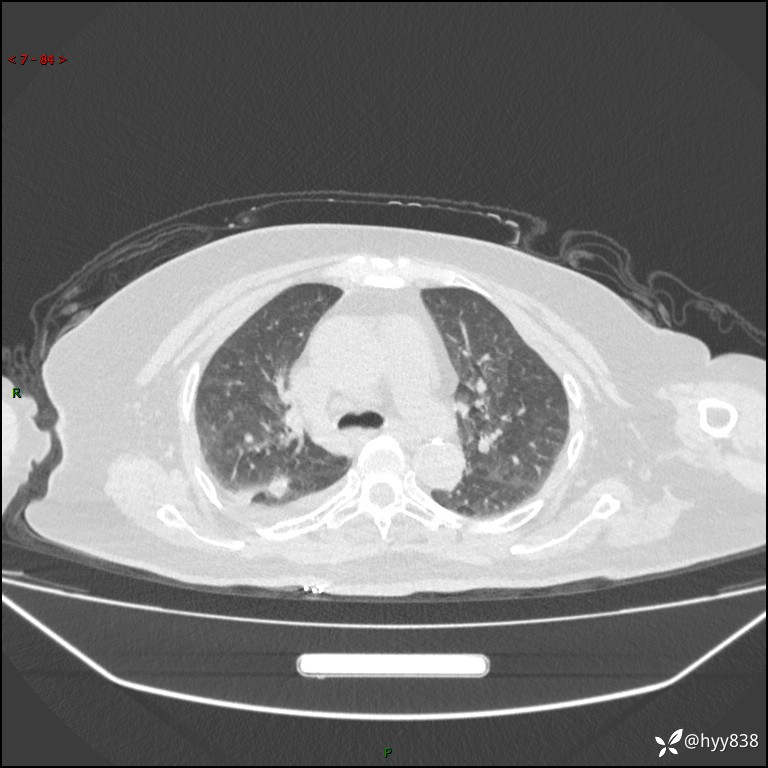

患者性别:女

患者年龄:57岁

简要病史:昏迷入院

胸部 CT平扫、